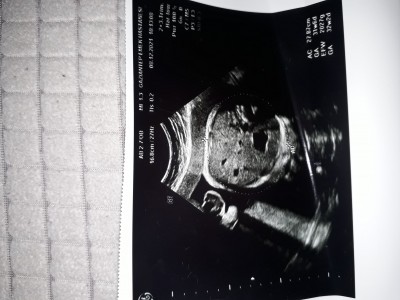

8 Aralık 2021 Hamilelikte Bebek Sağlığı kategorisinde (1 puan) sordu

Yüzü gibi duruyor ama

Gebelik haftası 34+1

Yok o yüzü değil yüzü olsa bile böyle çıkmaz kafa tasıdır yada karın bölgesidir

Yok canım karın bölgesi yüzü olsa belli olurdu

Ac yazıyor yani bu karın çevresi demek

Kafa tası üstten çekilmiş